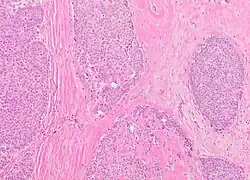

Pathology

The microscopic histopathology of typical PDCIS lesions (refer to adjacent high-power photomicrograph) prepared with a hematoxylin and eosin stain consists of mammary ducts that have papillary fronds (i.e. thin, finger-like or leaf-like structures) lined with one or several layers of neoplastic, columnar-shaped epithelial cells (i.e. tall, narrow cells with their nuclei close to the site of their ductal attachment).[4] The fronds have branching fibrovascular cores. Epithelial cells lining the fronds' inner surfaces commonly form solid, cribriform (i.e. large nests of cells perforated by many rounded, variably sized spaces), or micro-papillary patterns. There may be a second population of epithelial cells lining the papillae that have abundant clear cytoplasm in addition to the usual neoplastic epithelial cells which line the papillae. These cells, which are not myoepithelial cells, have been termed globoid cells.[7] They have eosinophilic cytoplasm (i.e. pink or red cytoplasm due to its uptake of eosin stain).[6] PDCIS tumors with these cells have been termed dimorphic variants of PDCIS.[3] Myoepithelial cells are typically present at the periphery of the fronds but absent within the involved ducts.[4][7] The presence of a fibrous capsule and/or absence of peripherally located myoepithelial cells are strong indicators that the tumor is an ESP rather than a PDCIS.[3] PDCIS tissues may also contain areas of "Comedo-type necrosis", i.e. areas where dead cells have accumulated.[6]